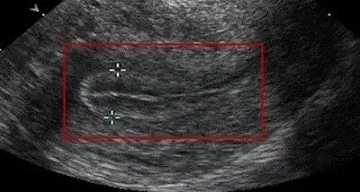

2、质地柔软:良好的内膜是B超声下的“三线”(如三条平行亮线),表明内膜分层清晰,血液供应良好。这意味着内膜处于晚期增殖或排卵期,结构松散,容忍度最好,最受欢迎的胚胎“搬进来”。

.png)

(三线征)图自网络,侵必删除